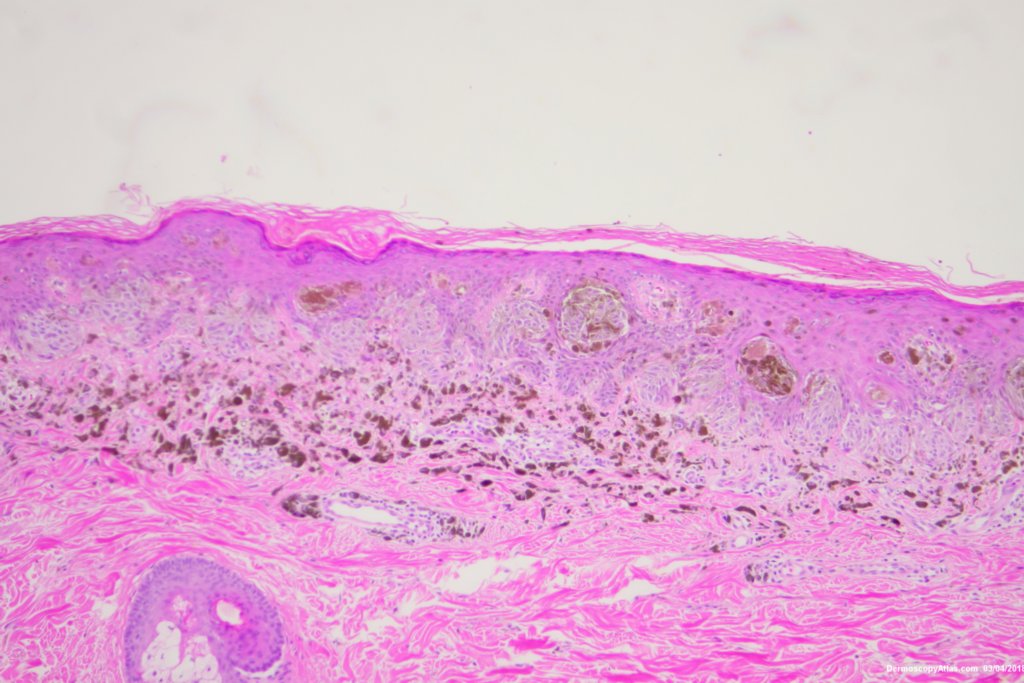

Diagnosis: Reed nevus

Sudden onset of a new pigmented lesion on the shoulder. Dermatoscopy shows an actively proliferating lesion with peripheral pseudopods that involve most of the circumference. Clinically this was either a Reed nevus or a Spitzoid melanoma. The histology favours a Reed nevus.